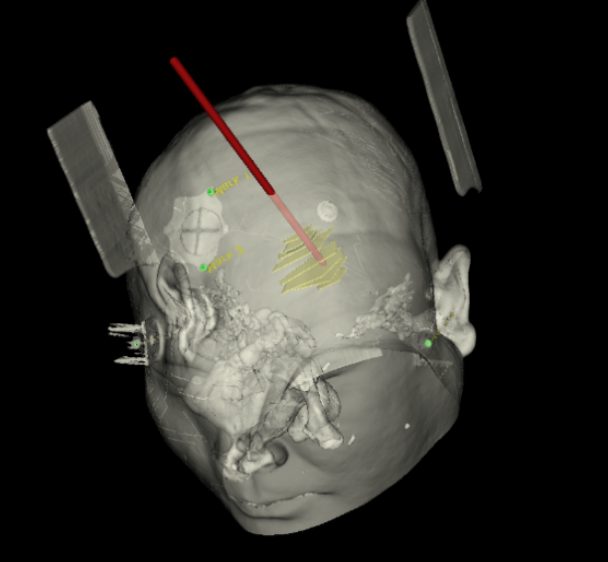

手術(shù)日當天,醫(yī)生團隊通過手術(shù)計劃系統(tǒng)為患者制定手術(shù)靶點及最安全的入顱路徑,隨后將手術(shù)規(guī)劃導入手術(shù)室的機器人當中。

實際手術(shù)時,機器人在幾分鐘內(nèi)就完成了空間注冊,機械臂在定位儀的引導下自動定位,準確鎖定靶點。